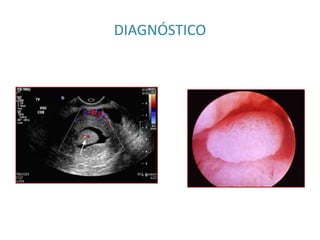

DIAGNÓSTICO

TRATAMIENTO